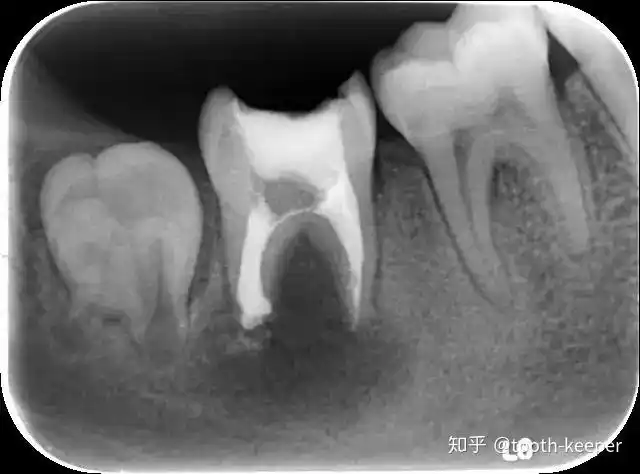

下颌第二磨牙c3型弯曲根管一例

下颌第二磨牙c形根管